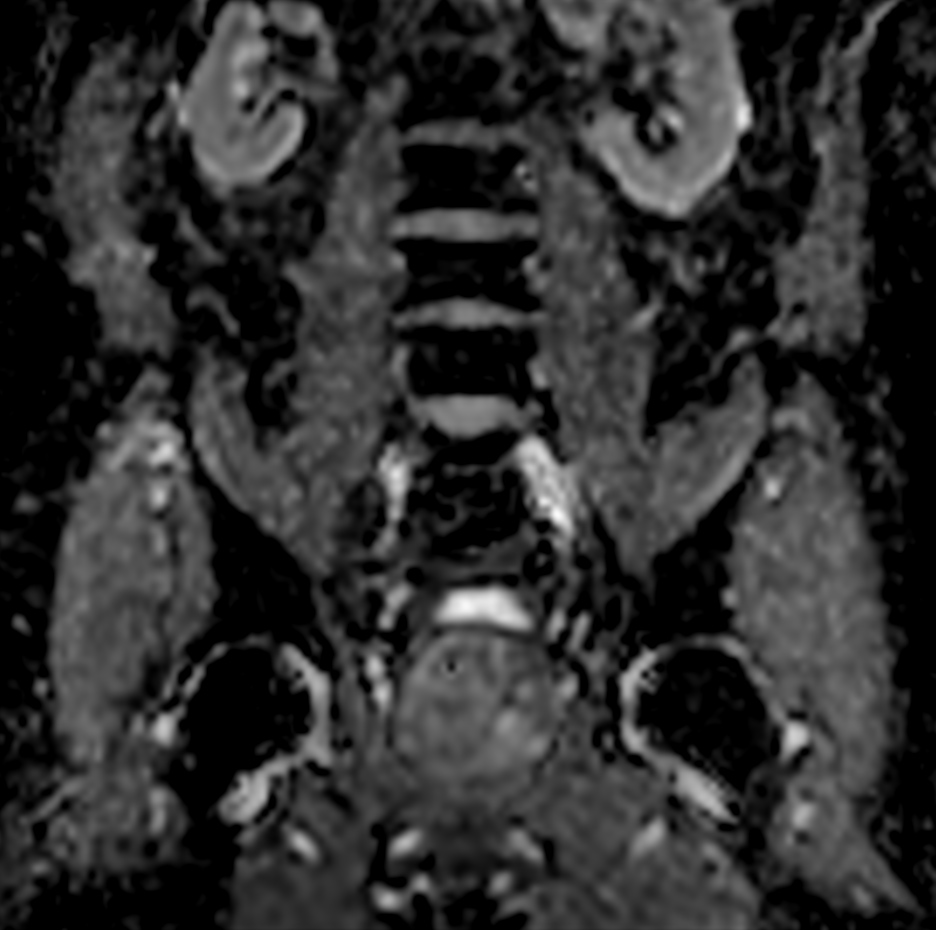

Multi-phase, contrast-enhanced prostate imaging

Patient with a prostate lesion. The ExamCard includes techniques for 3D imaging (PelvisVIEW, eTHRIVE) allowing for multiple image directions in one single scan, efficient fat-free imaging over large field-of-views (mDIXON XD), a multi-phase contrast-enhanced sequence (4D FreeBreathing) to improve imaging confidence and Compressed SENSE to accelerate the entire exam.

DWI b2000 large FOV

DWI b2000 large FOV (ADC)

DWIBS b1000

DWIBS b1000 (ADC)